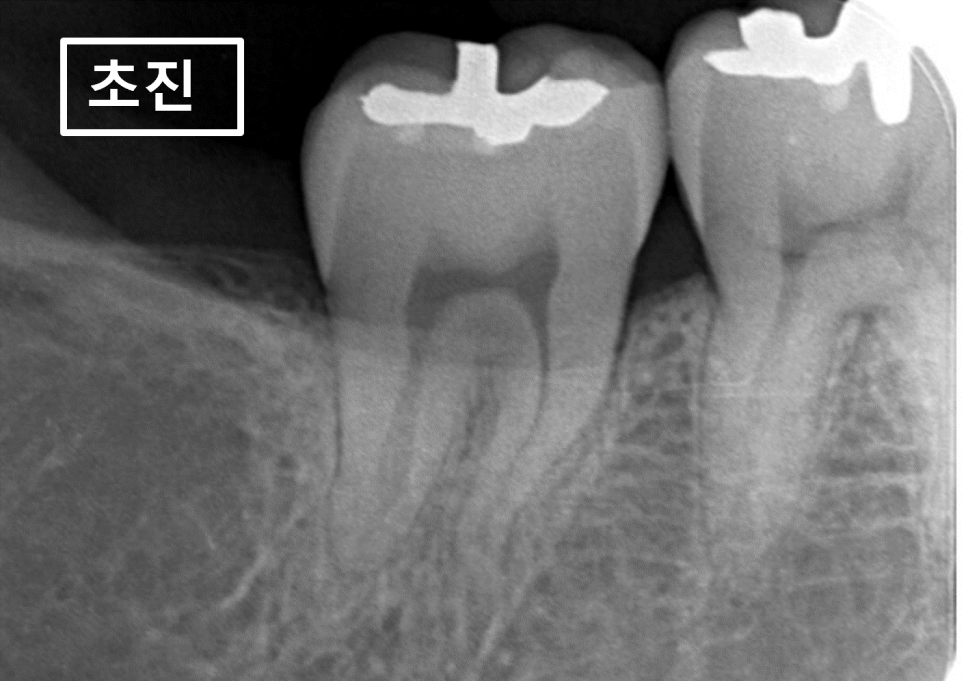

22.04.22(초진) – 45y 박OO님

” 오른쪽 아래 어금니가 씹을때찌릿해요.

처음에는 안그랬는데 요새는

가만히 있어도 욱신거릴때가 있어요 “ 라고 말씀하시며

1년전에 매탄동치과 바른본으로 내원하신 환자분의

x-ray 사진입니다.

1년전에 촬영한 확대해서 촬영된 x-ray 사진입니다.

환자분께서 불편하다고 하시는 점이

치과에 오셔서는 재현이 안되고

통증도 집에 있을때는 아픈데

치과에 오니 안아프다고 하셔서

바로 치료하지 말고 증상이 충분히

재현될때까지 기다려보자고 말씀드렸습니다.